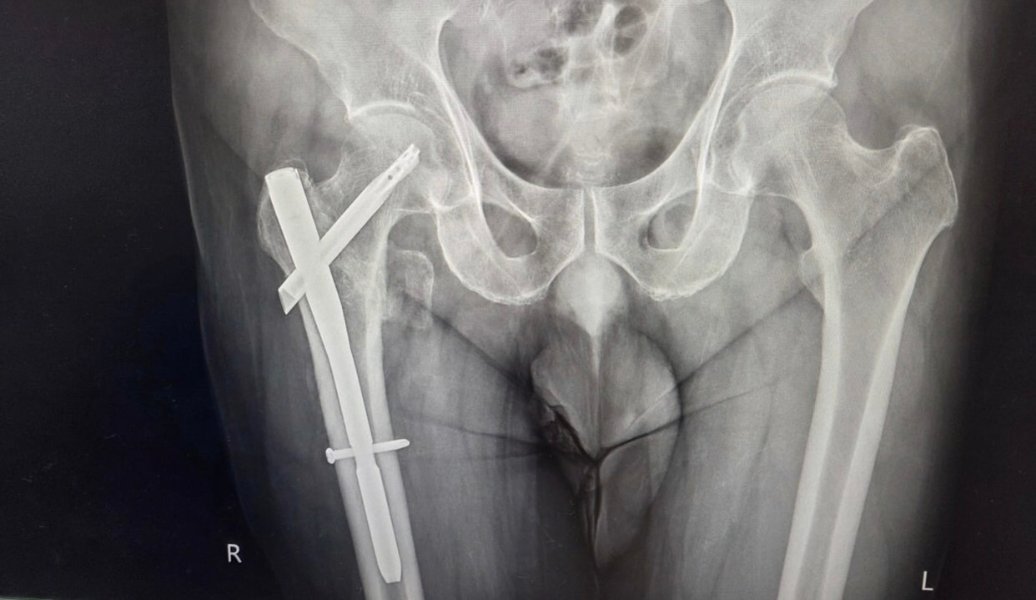

My gf is a travel guide. She has a bunch of Slovaks as customers. She packed them off at their hotel at 8pm and at 8pm she is on her own time. One of the daft <deleted> got a motor bike to go somewhere or other and crashed. Broke two ribs and both legs. She has been asked to go to the hospital to help out but her credit is maxed and can't get cash. Can I send her some cash. Isn't that the responsibility of the dumb stupid Slovaks. What is the betting they have no insurance. Sending cash for Thai families is one thing. I draw the line at dumb stupid tourists.